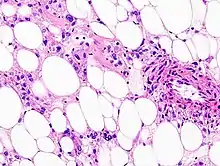

Histopathologic image of renal angiomyolipoma. Nephrectomy specimen. H&E stain. | |

PECs consist of perivascular epithelioid cells with a clear/granular cytoplasm and central round nucleus without prominent nucleoli.

PECs typically stain for melanocytic markers (HMB-45,[4] Melan A (Mart 1), Mitf) and myogenic markers (actin, myosin, calponin).